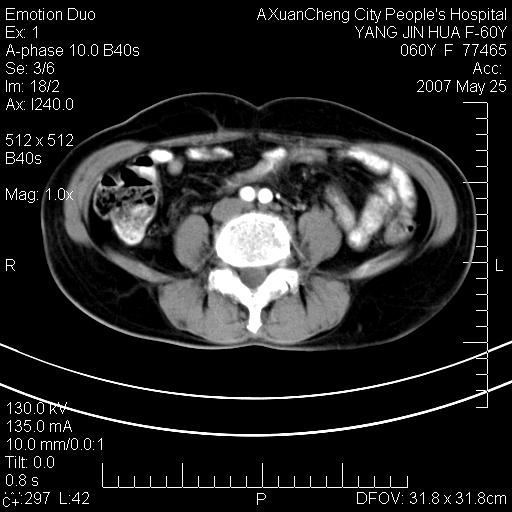

发现左侧腰背部包块40余年,逐渐长大,质软,局部表面可见扩张的血管影

左背部皮下良性肿瘤,密度不均,边界不清,内有脂肪、钙化,增强扫描无明显强化,血管平滑肌脂肪瘤?进一步诊断有困难,建议穿刺活检。

左侧背部皮下混杂密度肿块,结构较疏松,边缘欠光整,内有多发斑点状钙化,考虑:皮下血管瘤。

这个病理增强扫描之前,我们是考虑是血管瘤,可是现在增强后一点强化都没有,还能考虑是血管瘤吗